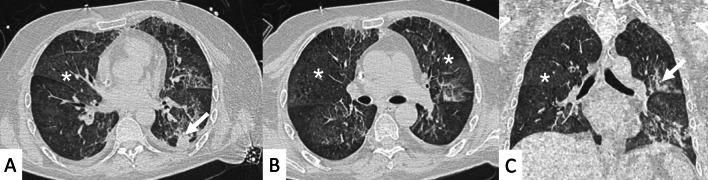

Connective tissue diseases (CTDs) include a spectrum of disorders that affect the connective tissue of the human body; they include autoimmune disorders characterized by immune-mediated chronic inflammation and the development of fibrosis. Lung involvement can be misdiagnosed, since pulmonary alterations preceded osteo-articular manifestations only in 20% of cases and they have no clear clinical findings in the early phases. All pulmonary structures may be interested: pulmonary interstitium, airways, pleura and respiratory muscles. Among these autoimmune disorders, rheumatoid arthritis (RA) is characterized by usual interstitial pneumonia (UIP), pulmonary nodules and airway disease with air-trapping, whereas non-specific interstitial pneumonia (NSIP), pulmonary hypertension and esophageal dilatation are frequently revealed in systemic sclerosis (SSc). NSIP and organizing pneumonia (OP) may be found in patients having polymyositis (PM) and dermatomyositis (DM); in some cases, perilobular consolidations and reverse halo-sign areas may be observed. Systemic lupus erythematosus (SLE) is characterized by serositis, acute lupus pneumonitis and alveolar hemorrhage. In the Sjögren syndrome (SS), the most frequent pattern encountered on HRCT images is represented by NSIP; UIP and lymphocytic interstitial pneumonia (LIP) are reported with a lower frequency. Finally, fibrotic NSIP may be the interstitial disease observed in patients having mixed connective tissue diseases (MCTD). This pictorial review therefore aims to provide clinical features and imaging findings associated with autoimmune CTDs, in order to help radiologists, pneumologists and rheumatologists in their diagnoses and management.

结缔组织病(CTDs)包括一系列影响人体结缔组织的疾病;它们包括以免疫介导的慢性炎症和纤维化发展为特征的自身免疫性疾病。肺部受累可能会被误诊,因为肺部改变仅在20%的病例中先于骨关节炎表现出现,且在早期阶段没有明确的临床发现。所有肺部结构都可能受累:肺间质、气道、胸膜和呼吸肌。在这些自身免疫性疾病中,类风湿关节炎(RA)的特征是普通型间质性肺炎(UIP)、肺结节和伴有空气潴留的气道疾病,而系统性硬化症(SSc)常表现为非特异性间质性肺炎(NSIP)、肺动脉高压和食管扩张。NSIP和机化性肺炎(OP)可见于多发性肌炎(PM)和皮肌炎(DM)患者;在某些情况下,可观察到小叶周围实变和反晕征区域。系统性红斑狼疮(SLE)的特征是浆膜炎、急性狼疮性肺炎和肺泡出血。在干燥综合征(SS)中,HRCT图像上最常见的表现是NSIP;UIP和淋巴细胞间质性肺炎(LIP)的报道频率较低。最后,纤维化NSIP可能是混合性结缔组织病(MCTD)患者中观察到的间质性疾病。因此,本图像综述旨在提供与自身免疫性CTDs相关的临床特征和影像学表现,以帮助放射科医生、呼吸科医生和风湿病科医生进行诊断和管理。